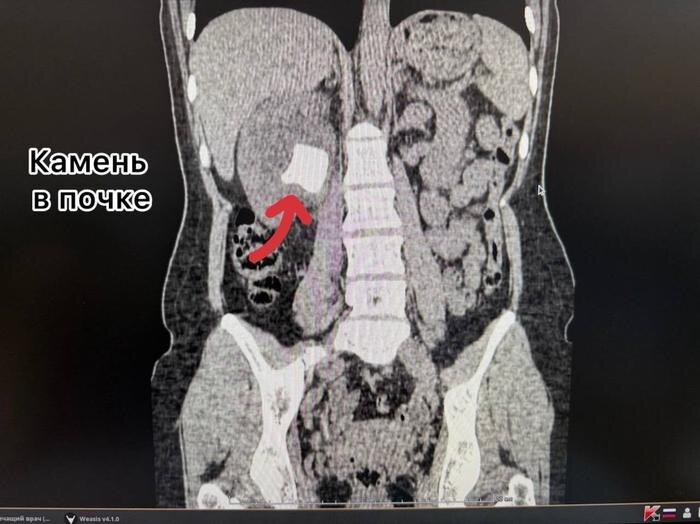

Выяснилось, что мочеточниковый стент был установлен женщине два года назад, но по какой-то причине его своевременно не извлекли. В результате инородный предмет затвердел, а в почке и мочевом пузыре пациентки образовались конкременты. Медики провели сложную многоэтапную операцию, в ходе которой одновременно удалили как сам стент, так и образовавшиеся в органах камни.

"Через один минимальный прокол в пояснице (метод перкутанной нефролитотрипсии) с помощью ультразвука был разрушен и удалён почечный камень. Одновременно, через естественные пути, современным лазером Urolase+ Premium был раздроблен и извлечен камень из мочевого пузыря и стент. Операция проводилась с применением эндоскопического оборудования и под рентген-контролем, что гарантировало высочайшую точность", - говорится в сообщении "Тысячекоечной больницы".